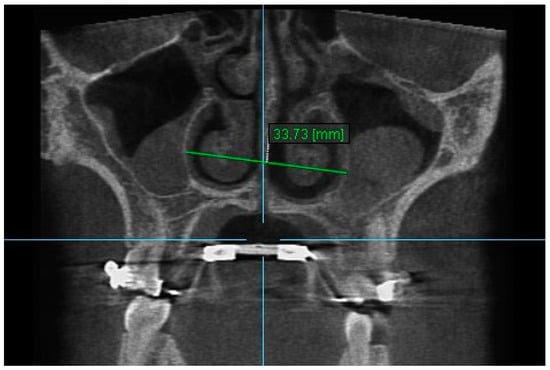

10. Aperture of Midpalatal Suture 10: The distance between the inner points of posterior median palatine suture, bilaterally in posterior nasal spine (PNS) (Figure 12).

Figure 12.

Aperture of Midpalatal Suture 10.